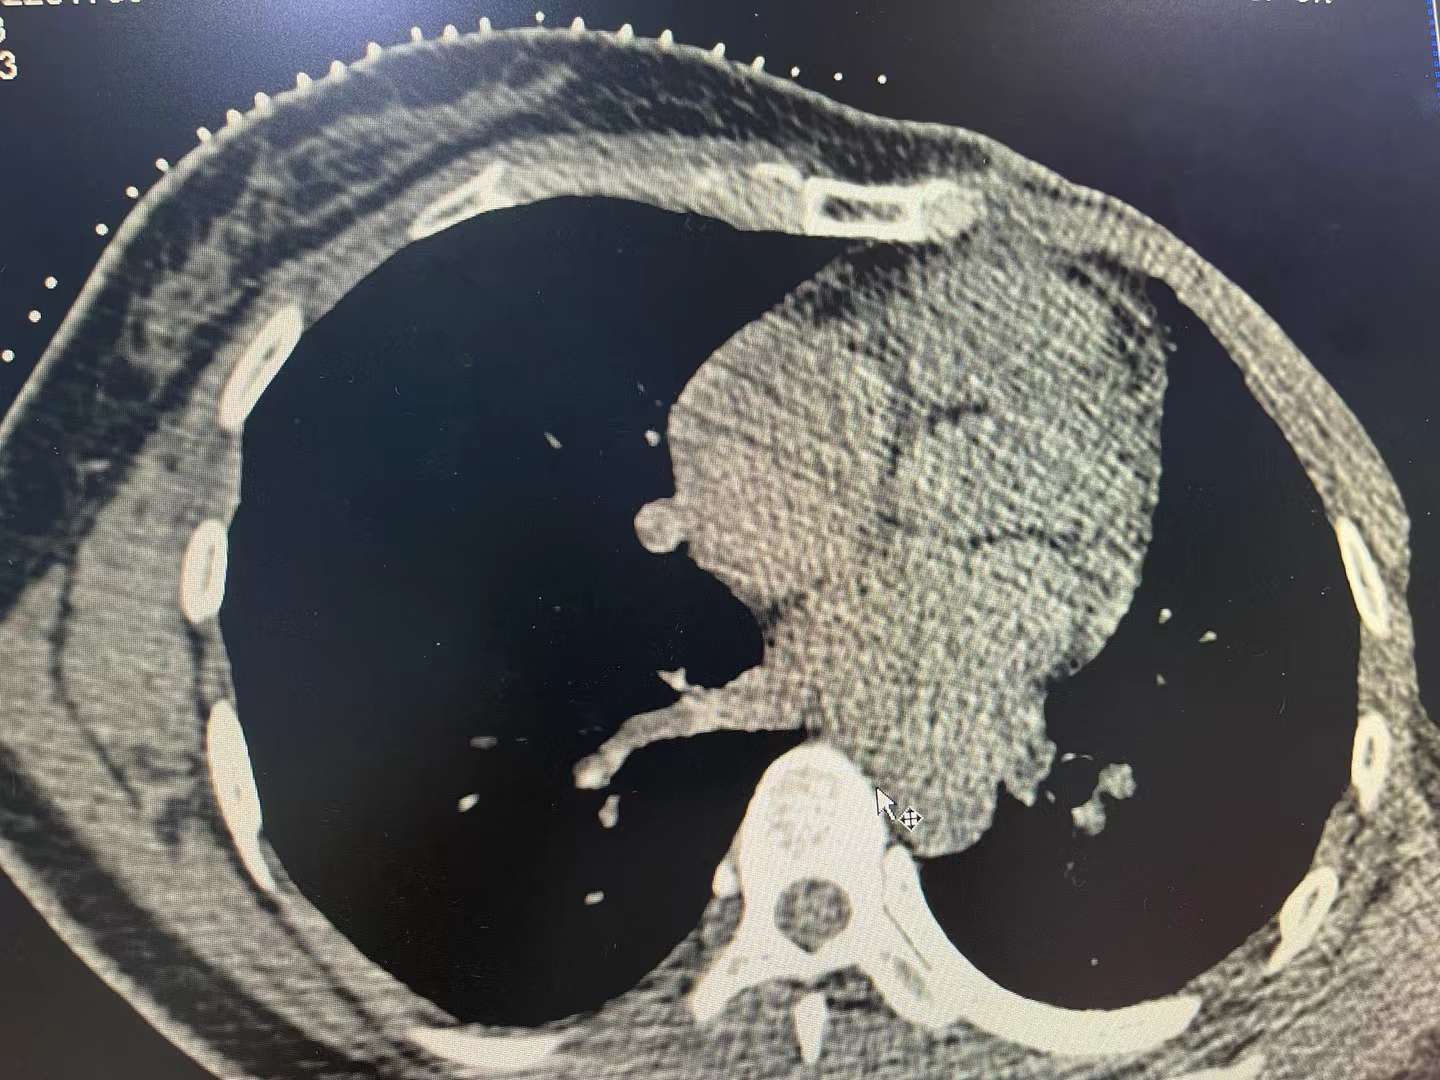

前两天的粒子植入术是教授亲自做的,16颗粒子布在那个0.9✘1.1的转移灶上。主任说病灶离心脏太近不适合消融,做粒子是一样的。为了巩固治疗,我还要做一次化疗栓塞。两天的空挡里我去见了原来肿瘤医院的医生,他看了我留在他那里的所有片子。那个长得刁钻的瘤子去年六月份复查还是个很小的点。他说我这种情况可以推荐我入实验组试药,如果我做了其他治疗就不能进组了。我不敢告诉他我已经做了手术介入。他说话的样子有些生气,我借口考虑几天便从办公室退出来了,他还把负责入组的小医生电话给了我。我知道他是为我好,希望我能以最经济的方式接受全身化疗。但是我自己不想那么早走到那一步。

我本来是带着伞去见医生的,出来时却忘了,我也不想再拿回来。脑子有点乱, 冷冷的冰雨浇在我的脸上。公交车上,我又把最近几个月发生的事情捋了一遍。上个月在本地三甲医院做了大复查,除了肺其他地方都没有发现问题。肺上的瘤子离心脏很近,当地医生说无法穿刺,建议我观察或者petct。我问医生是不是做了pet是怀疑转移就可以上化疗,他说病理才是金标准。我当时就觉得既然又不能穿刺又哪来的病理呢?pet又贵,到最后还是有可能不能确诊。他说为了一个不确定的还那么小的瘤子就给你上化疗,你觉得划得来吗?想想也是,于是出院回家。

我本意还是倾向于做介入。后来,这边的教授给我做了增强ct,觉得恶性可能性很大,同样因为离心脏太近,不能做消融便放了粒子。为了保险起见,预计给我进行一次化疗栓塞,用的吉西他滨和卡铂。这两天,一直为了原主治医生推荐入组的事情患得患失,现在想也没必要了。只是推荐入组还不一定能筛查过关,我相信几个医院的医生都不敢做的穿刺,他们也未必可以,再加上常年白细胞低,基因检测brc两项突变都是阴性,能不能入组还得一说,即使入组了药物对我有不有效又还得一说。至少现在能让我暂时逃离三个月,茫茫求生路,到处都是变数,一切皆是天意。

打不死的小妖精发个图,会看的给看看。